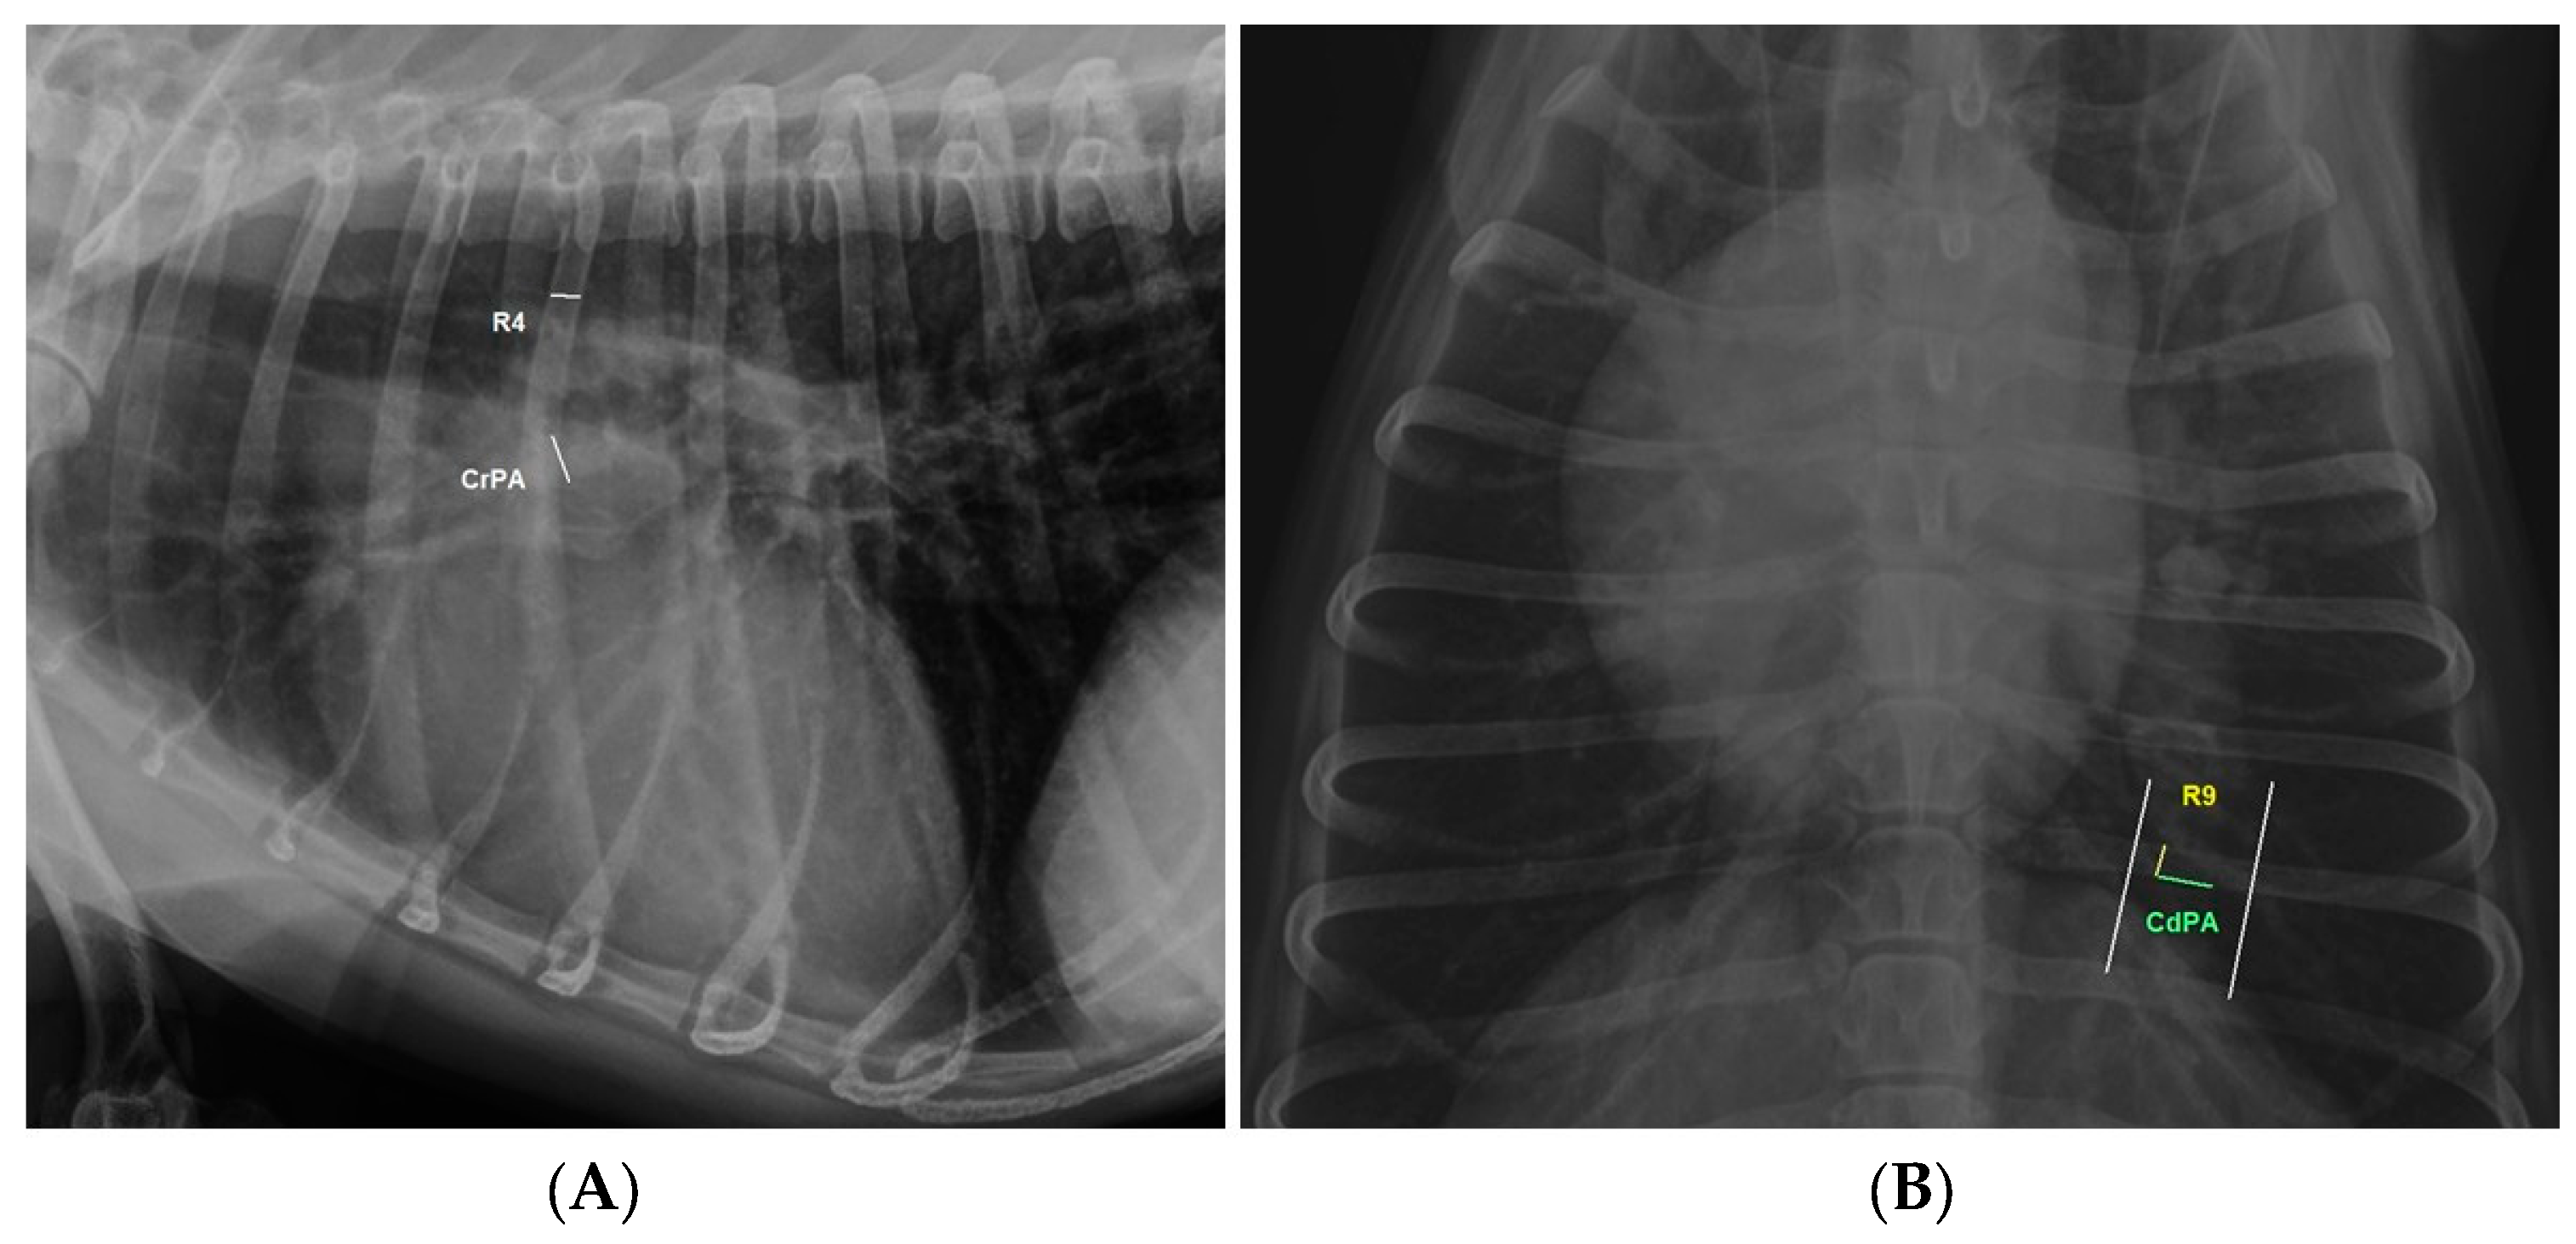

| IDAPD-CRPA/R4 | −0.4344274 *** | Moderate negative correlation |

| CRPA/R4 | 0.959 | 0.77 | ≥1.08 | 87.5% | 70% |

| CrPA/R4 | 4.31 | Large effect |